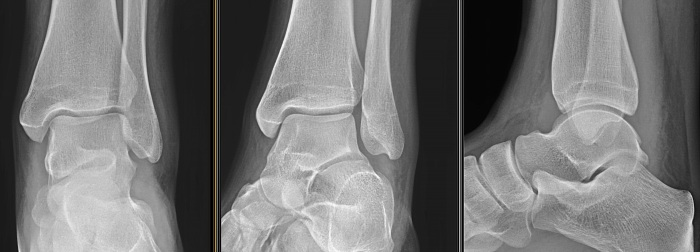

СКЛАДНИЙ СУГЛОБ (ЯК ВИЛКА). Є ВСІ ПЕРЕДУМОВИ ДЛЯ РОЗТЯГНЕННЯ ЗВ'ЯЗОК І ЗМІЩЕННЯ КІСТОК. РОЗПІЗНАЙТЕ СУГЛОБ.

варіанти відповідей

СУГЛОБ УТВОРЕНИЙ СУГЛОБОВИМИ ПОВЕРХНЯМИ ЛАТЕРАЛЬНОЇ І МЕДІАЛЬНОЇ КІСТОЧКИ ТА ТІЛОМ ТАРАННОЇ КІСТКИ. РУХИ НАВКОЛО ФРОНТАЛЬНОЇ ОСІ. ЧАСТО - РОЗТЯЖІННЯ, ВИВИХИ, РОЗРИВИ, ПЕРЕЛОМИ. РОЗПІЗНАЙТЕ СУГЛОБ.

КОЛІННИЙ С.

ГОМІЛКОВО-СТОПНИЙ С.

КУЛЬШОВИЙ С.

ЛІКТЬОВИЙ С.

ПЛЕЧОВИЙ С.

ПРОМЕНЕВО-ЗАП'ЯСТКОВИЙ С.